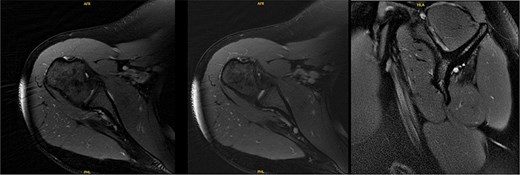

Six years following decompression, the patient presented for right shoulder pain and fatigue without new injury. Post-collegiately, she coached volleyball. MRI revealed a diffusely atrophic infraspinatus muscle belly (Fig. 3). On examination, she demonstrated persistent diminished infraspinatus, supraspinatus, and teres minor strength, pain in the Aber position, mild anterior apprehension, and a positive (+1) Sulcus sign. She proceeded with posterior capsular stretching and cuff strengthening.

MRI 6 years after decompression revealed a diffusely atrophic infraspinatus muscle belly.